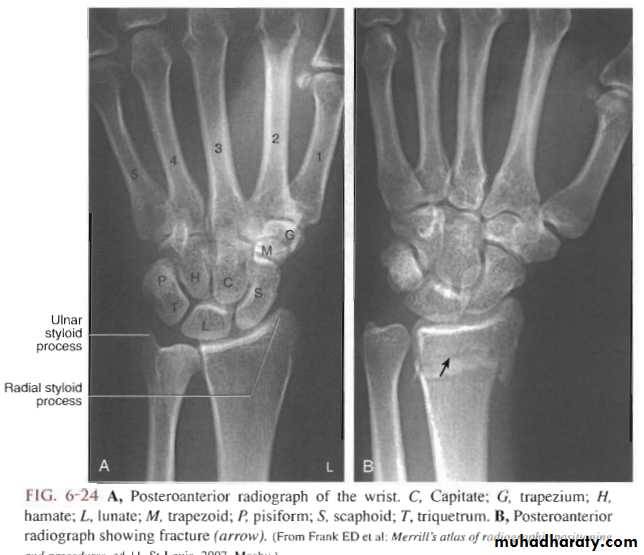

Radiological evaluation

Lateral radiograph